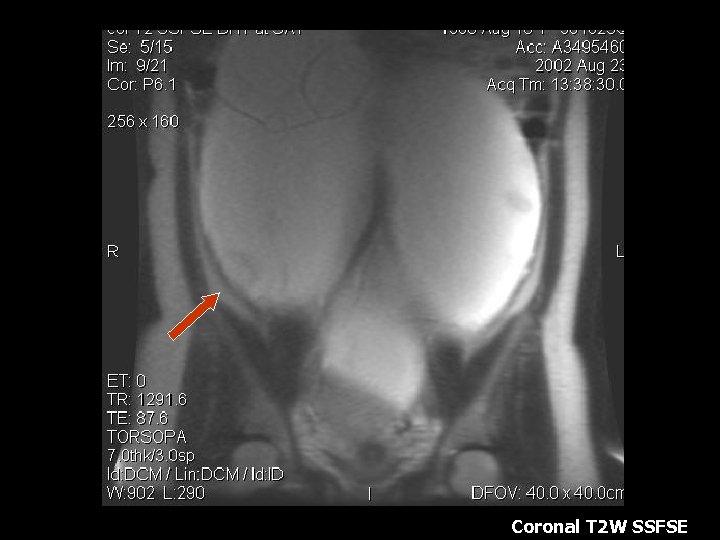

Ovarian Torsion • Fifth most common gynecologic diagnosis(8). • Symptoms – Abdominal pain, nausea and vomiting(8). • Early diagnosis can salvage ovarian function(10%)(8). • Torsion produces circulatory stasis, initially venous, then progresses to arterial(9). • Predisposing factors include ipsilateral adnexal mass, usually benign(9). • Teratoma is the most common benign neoplasm(9).

Torsion • • • MRI findings: Tube thickening(84%) Ovarian cystic mass(76%) Ascites(64%) Deviation of the uterus(36%) Less Common: Hemorrhage and hemoperitoneum

Coronal T 2 W image